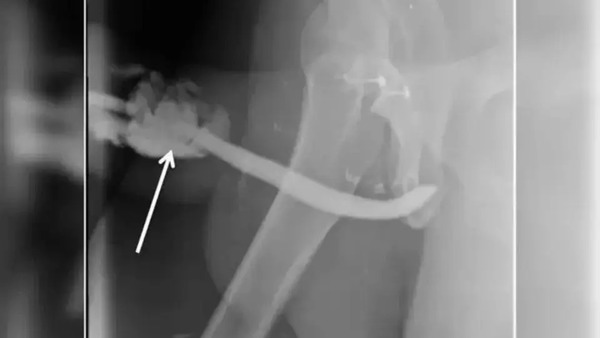

O tanzaniano teve de passar por uma cirurgia de emergência no hospital de Kilimanjaro para que o órgão fosse reconstruído, já que o órgão torcido e em um formato que os médicos descreveram como semelhante a um balão. Depois do procedimento e do período de recuperação, o pênis do paciente voltou a funcionar normalmente.

O caso dele foi descrito em um artigo publicado neste mês de maio na revista especializada International Journal of Surgery Case Reports.